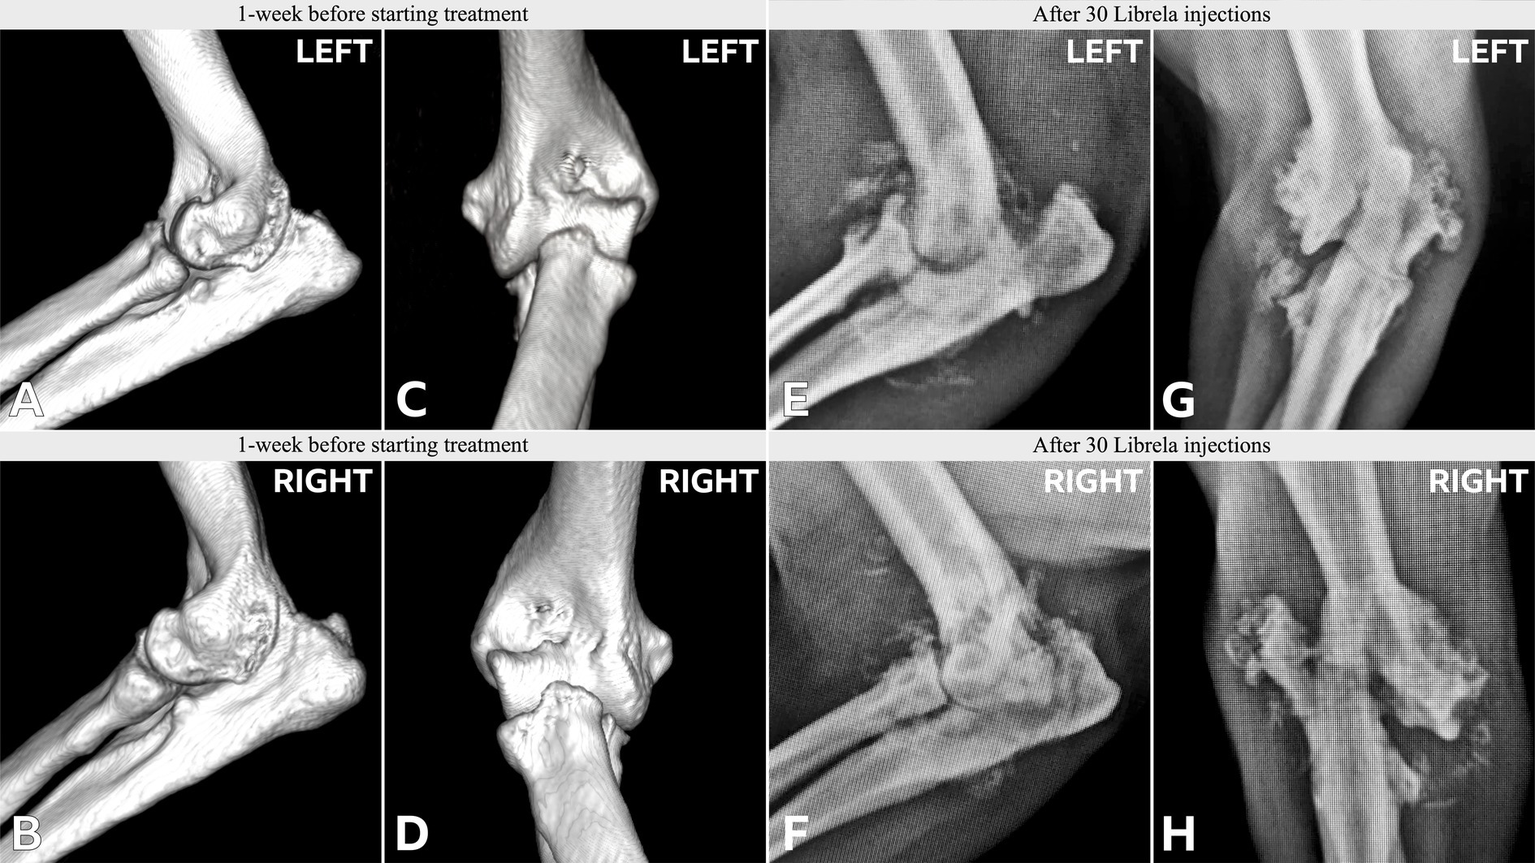

Figure 9

Case 14, a 5.5-year-old Labrador Retriever, received Librela to treat mild elbow dysplasia. Tarsal swelling and hindlimb lameness developed, and this CT scan was acquired after 16 doses. Note the marked bilateral soft tissue swelling and palisading calcaneal periosteal reaction. AER: A report was filed for suspected RPOA because both hocks were clinically normal before treatment and developed severe OA with bilateral talar insufficiency fractures after treatment.

Figure 10

Case 15, an 8-year-old English Bull Terrier treated with Librela for elbow dysplasia developed tarsal swelling and hindlimb lameness within 3 weeks of the first dose. (A,B) Radiographs acquired after 2 Librela injections show moderate bilateral arthrosis which progressed rapidly, culminating in left tibiotarsal luxation (C–E). Synovial fluid analysis ruled out inflammatory arthropathy or tick-borne disease. AER: The MAH filed a report using the diagnostic term “swollen joint”, and misclassified the reaction as not serious and recovered/resolving. Following communication from the attending veterinarian regarding the translation error, the MAH escalated the enquiry to their Global Pharmacovigilance Team, who concluded that the observed pathology was consistent with erosive immune-mediated polyarthritis (IMPA), despite normal synovial fluid test results (Supplementary Figure S8).

Figure 11

Radiographs from Case 17, a 5-year-old Springer Spaniel, before and after 20 Librela injections.

Figure 12

Case 18, a 5.5-year-old Australian Shepherd, had stable stifle joints before starting Librela. AER: The attending specialist filed a report for suspected RPOA to the MAH, who submitted an AER for ligament ruptures, fractures, and joint subluxation/luxations. Their report designated this reaction as not serious (Supplementary Figure S9).